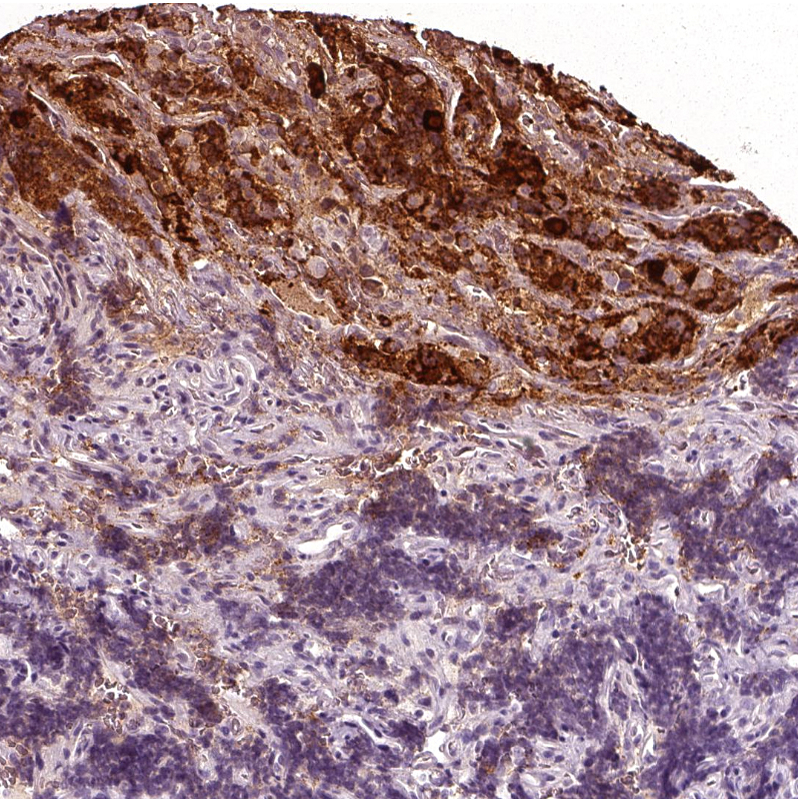

Immunohistochemistry analysis in human placenta and prostate tissues using HPA029698 antibody. Corresponding CGA RNA-seq data are presented for the same tissues.